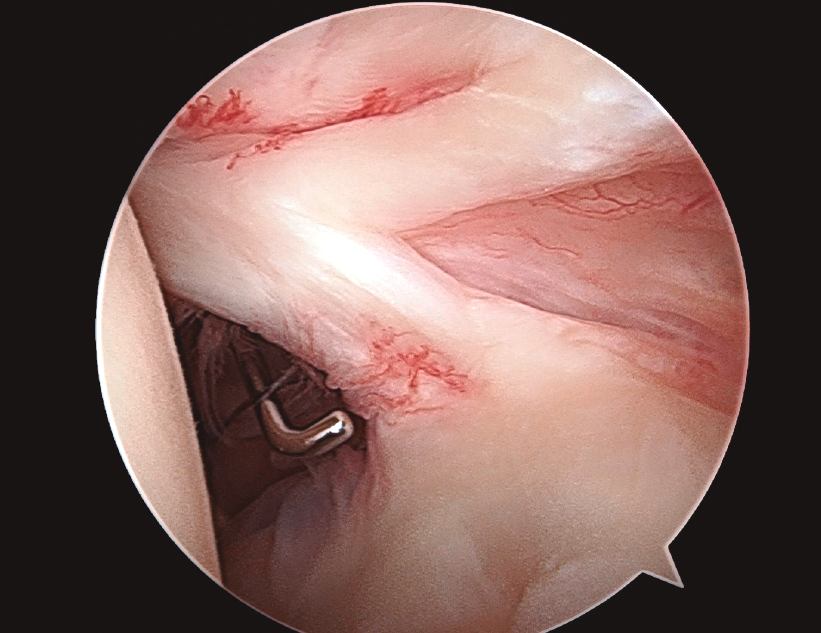

Se han descrito diferentes variantes anatómicas de la porción larga del bíceps (PLB), pero una de las más frecuentes es tener una PLB doble.

Mostramos una variante de su inserción, una a nivel superior de la glena y la otra en el espesor del supraespinoso.